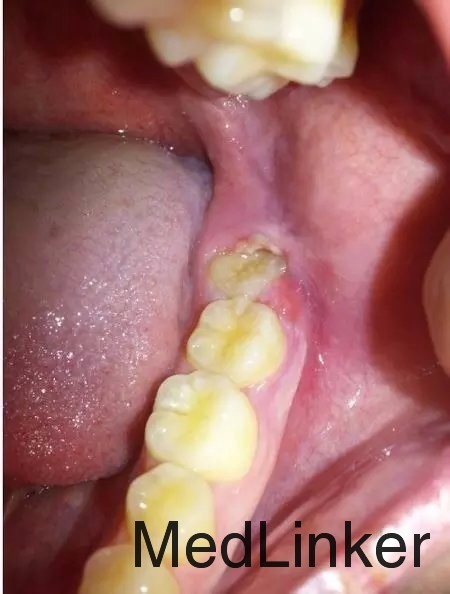

智齿冠周炎

王白宇 女 23 近一周左下后牙疼痛,伴低烧,张口受限,吞咽疼痛,伴颊侧肿痛,未作过治疗,前来就诊。